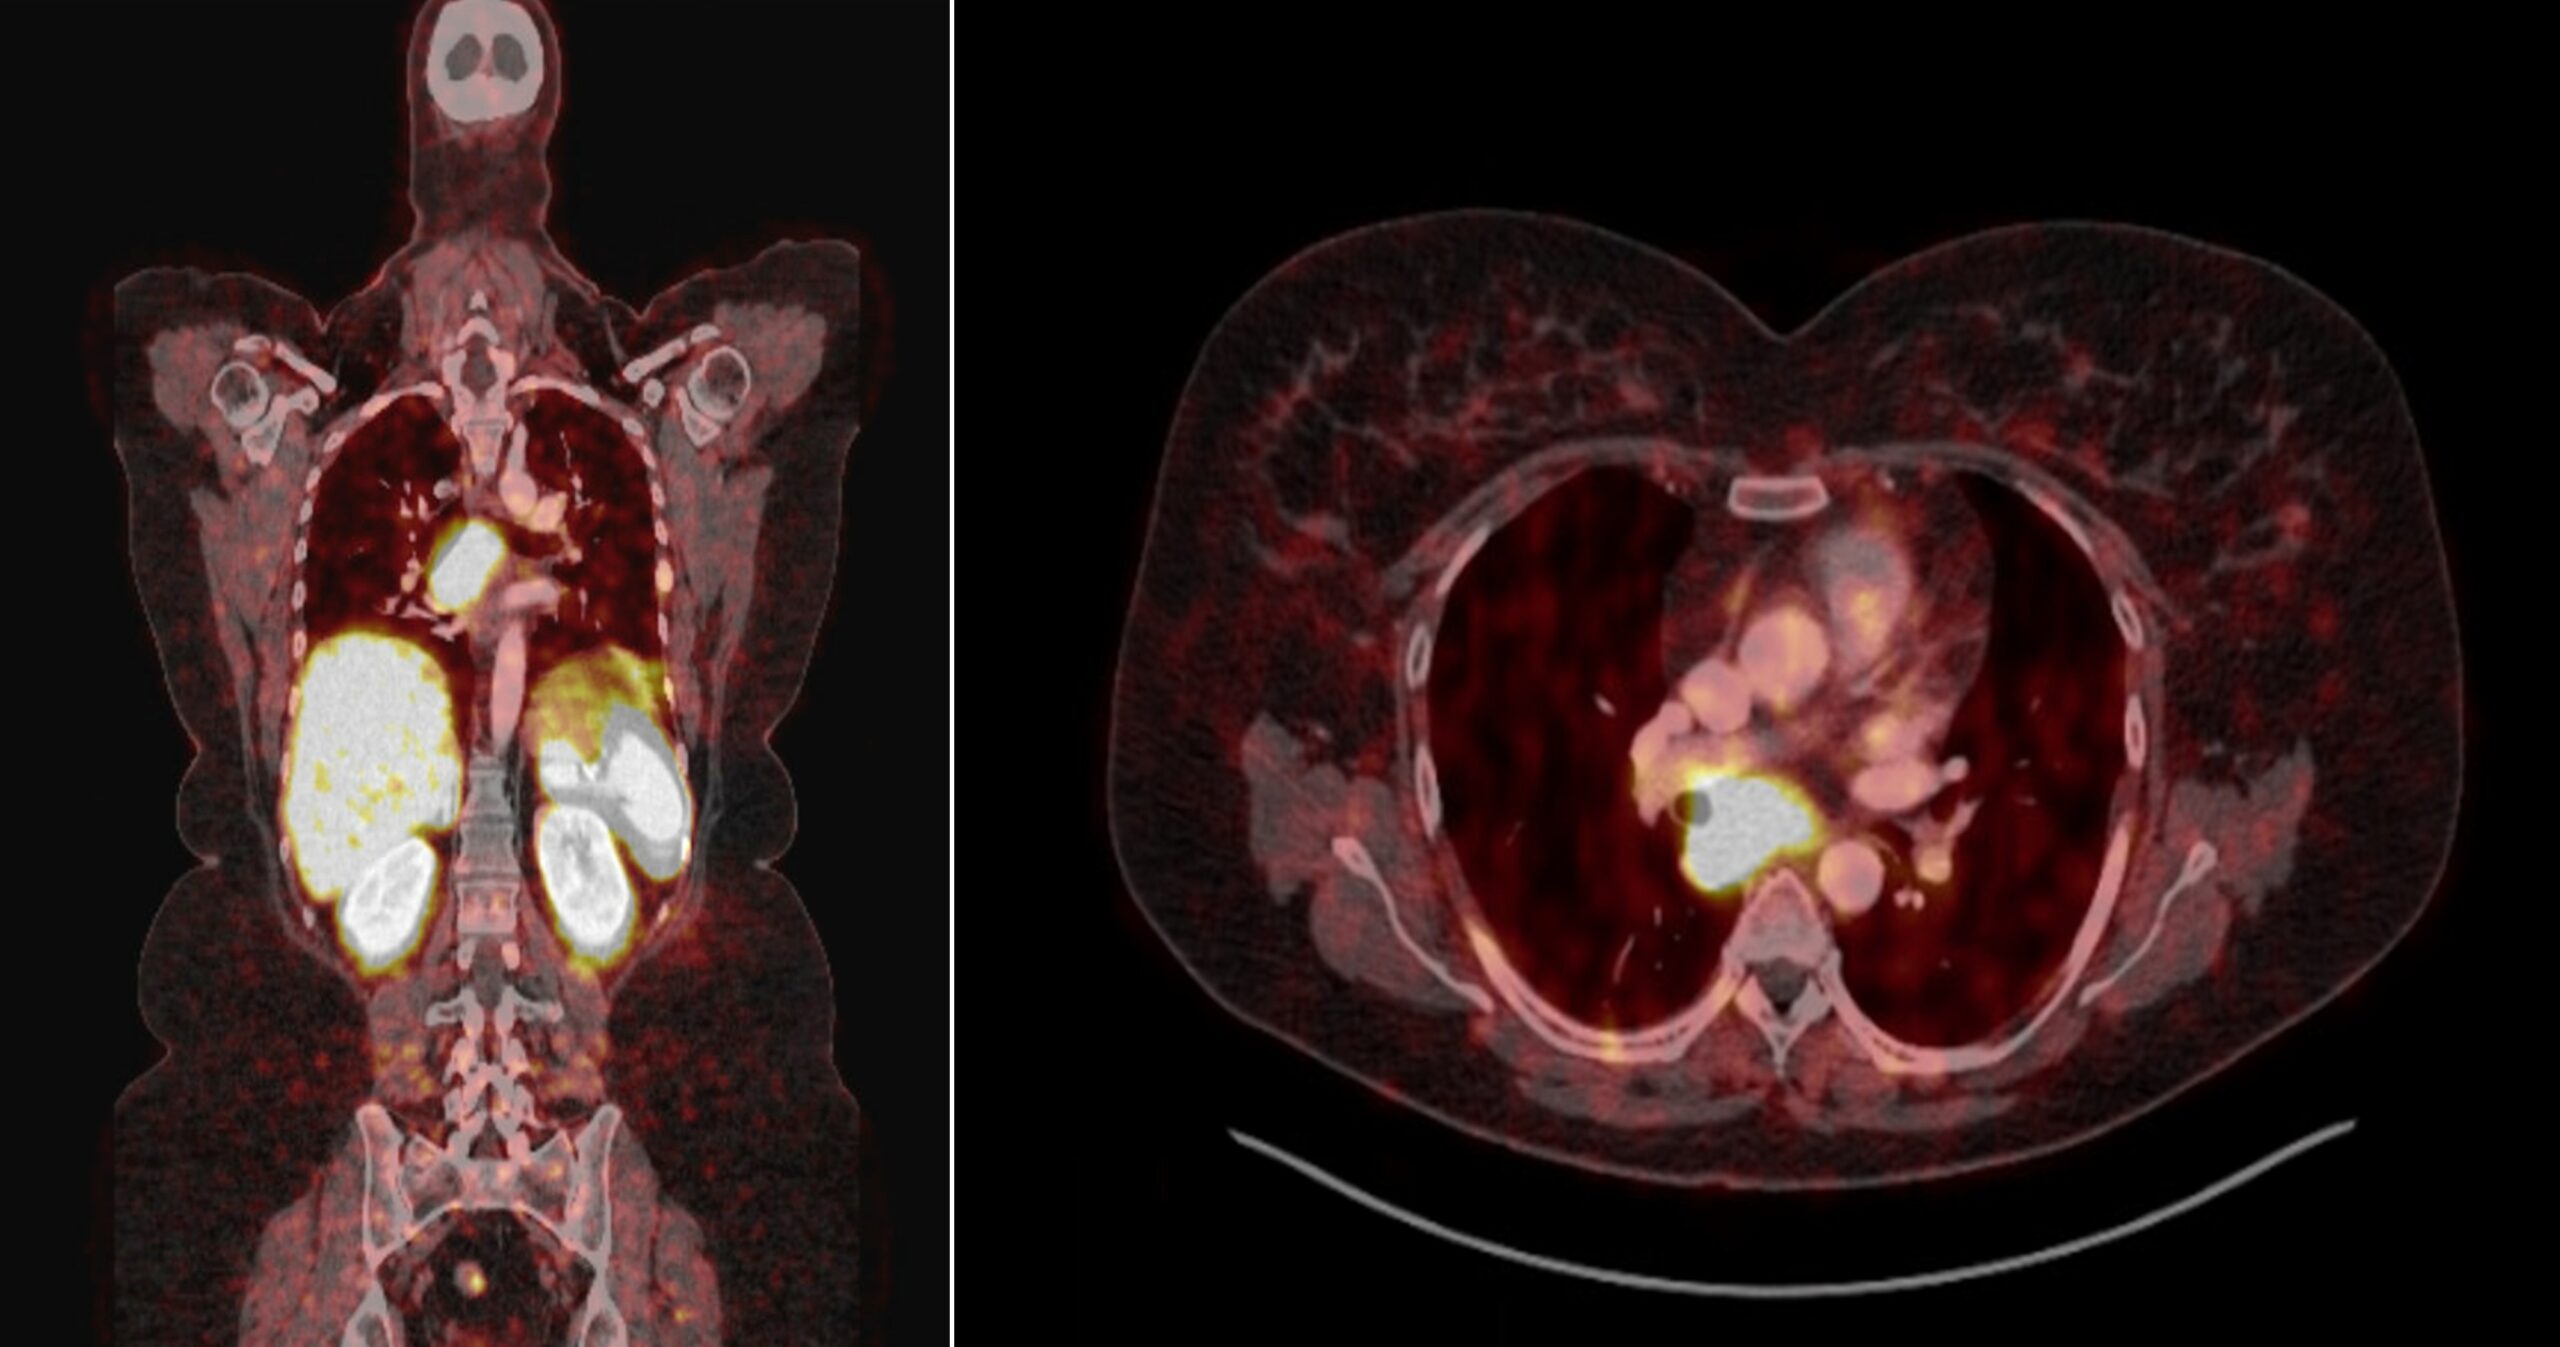

Lynch syndrome is a genetic condition associated with tumours of the colon, reproductive organs, and urinary tract. Less commonly, neuro-endocrine tumours have also been reported. We describe the first case of a Lynch syndrome patient presenting with a neuroendocrine lung tumour manifesting as cortisol excess (Cushing’s syndrome) in a middle-aged woman.

In addition to the germline MLH1 splice site mutation, genetic analysis revealed a complete gene deletion of MLH1 as somatic second hit, confirming the tumor’s link to Lynch syndrome. Furthermore, we provide a comprehensive review of the existing literature on neuroendocrine tumors occurring in Lynch syndrome. (By Kevin Van Compernolle, on behalf of co-authors Jacques Van Huysse, Kathleen Claes, Ellen Denayer, Marie Bex, and Annick Van den Bruel, https://jmg.bmj.com/content/early/2025/11/23/jmg-2025-110900 )